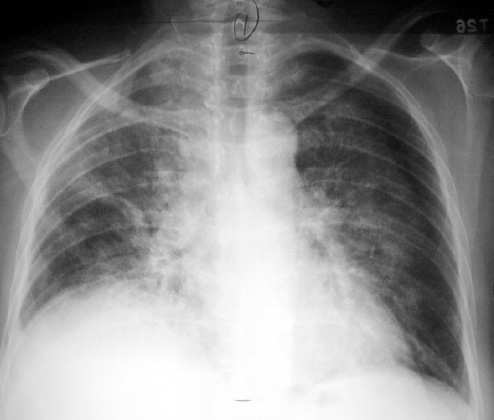

Methotrexate Lung